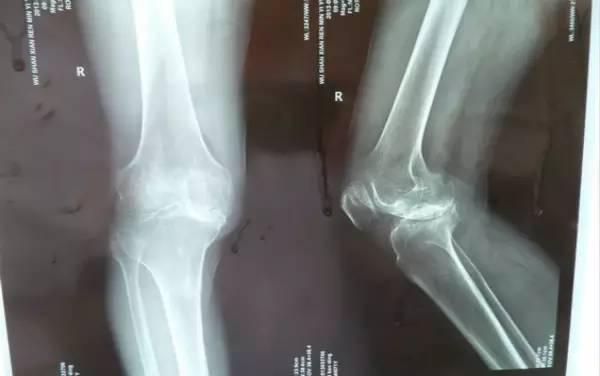

作过那些诊断性的检查:

X线片、CT、MRI、断层摄片、超声检查、同位素骨扫描、椎间盘造影等?在脊柱的什么节段?在那里进行了这些检查?检查的结果如何?